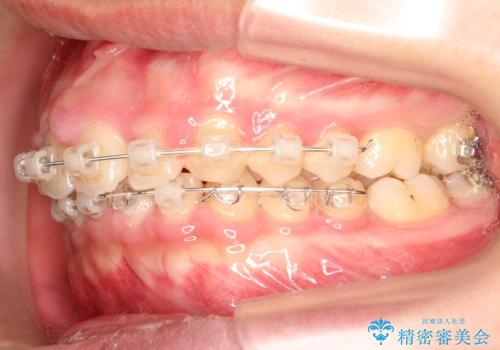

検査の結果、抜歯なし/ワイヤー矯正にて治療を行いました。

また、成長期終盤の男の子だったため成長の余力(下顎を前に牽引んし成長を促進する)を期待しアドバンシンクという装置を使い、下顎の骨の成長を利用した矯正治療を行いました。